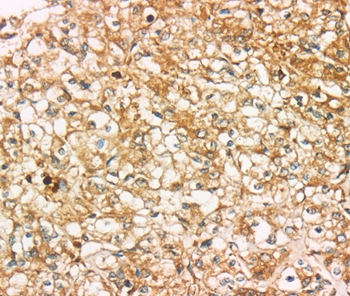

Immunohistochemical analysis of paraffin-embedded Human tonsil cancer tissue using #37925 at dilution 1/35.

Immunohistochemical analysis of paraffin-embedded Human prostate cancer tissue using #37925 at dilution 1/35.